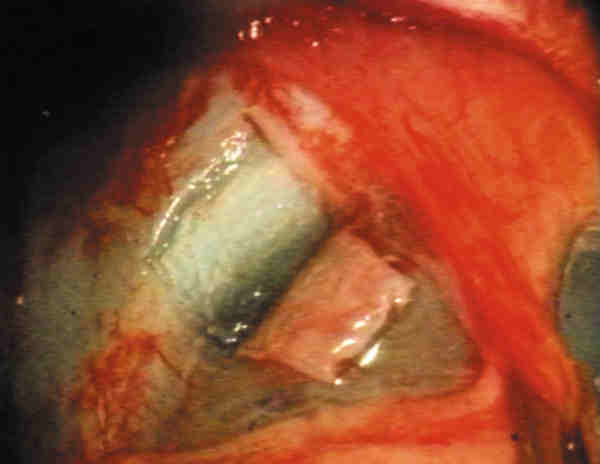

7. Tallado del colgajo escleral (figura 1): El tamaño depende especialmente de las preferencias del cirujano. Recomendamos 3-4 mm en sentido circunferencial y 3 mm en sentido radial. Las referencias se realizan respecto a la unión corneolimbar. Si se va a emplear MMC su profundidad será de la mitad del espesor escleral; si no es así, recomendamos 1/3 de dicho espesor.

08-01.jpg (12128 bytes)

Figura 1. Tallado del colgajo escleral.